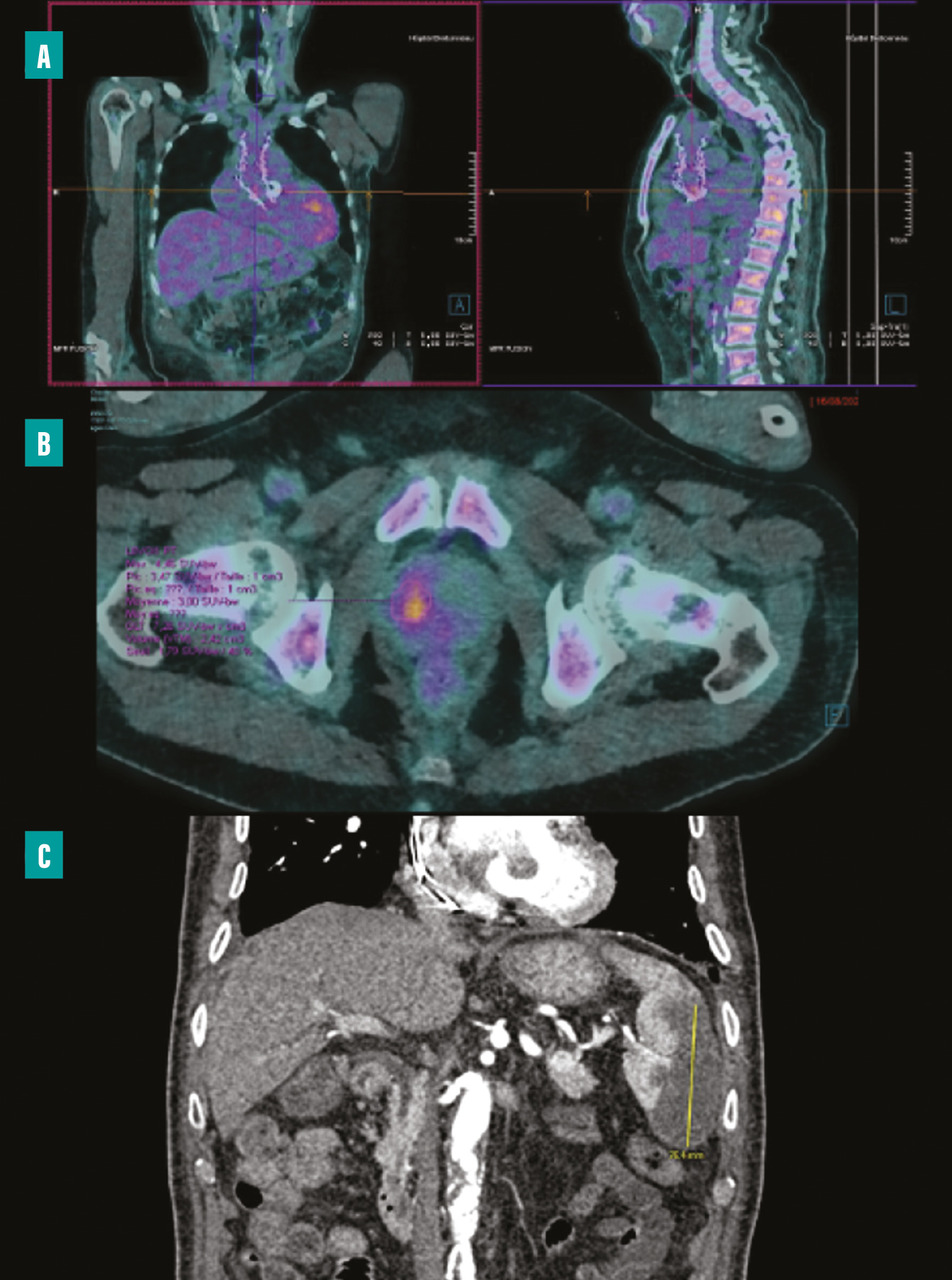

La tomographie par émission de positons (TEP-scanner au 18F-FDG) et la scintigraphie aux leucocytes marqués (moins sensible que la TEP) permettent, en cas de fixation anormale sur du matériel ou l’endocarde adjacent, d’avoir un critère diagnostique majeur.4,9 Elle permet aussi de détecter des lésions emboliques périphériques ou des lésions secondaires infectieuses (fig. 2 ).

La sensibilité de ces examens est bonne pour le diagnostic d’EI sur matériel mais assez faible sur valve native et ne permet donc pas d’éliminer le diagnostic en cas de négativité. Dans les trois premiers mois postopératoires d’une chirurgie de remplacement valvulaire, une fixation focale intense ou hétérogène est associée à un diagnostic d’infection, alors que les changements liés à une inflammation postopératoire peuvent être différenciés et observés au-delà des trois premiers mois. L’examen peut donc être réalisé quel que soit le délai de la suspicion par rapport à la chirurgie.

Un scanner corps entier avec injection permet de rechercher un abcès splénique ou autre (fig. 2 ) et d’analyser les vaisseaux périphériques afin de dépister une complication vasculaire à type d’embole, d’anévrysme mycotique. Il n’est pas recommandé à titre systématique, mais la détection de lésions distales ajoute un critère mineur et peut permettre de rendre le diagnostic certain. Il peut aussi aider à la recherche d’autres foyers infectieux et ainsi identifier un diagnostic alternatif, le TEP-scanner étant, dans ce cas, supérieur.

Le développement des techniques hybrides associant médecine nucléaire et scanner apporte de nouveaux outils d’imagerie pour les situations diagnostiques difficiles d’EI, particulièrement sur matériel.La tomographie par émission de positons (TEP-scanner au 18F-FDG) et la scintigraphie aux leucocytes marqués (moins sensible que la TEP) permettent, en cas de fixation anormale sur du matériel ou l’endocarde adjacent, d’avoir un critère diagnostique majeur.4,9 Elle permet aussi de détecter des lésions emboliques périphériques ou des lésions secondaires infectieuses (

Un scanner corps entier avec injection permet de rechercher un abcès splénique ou autre (